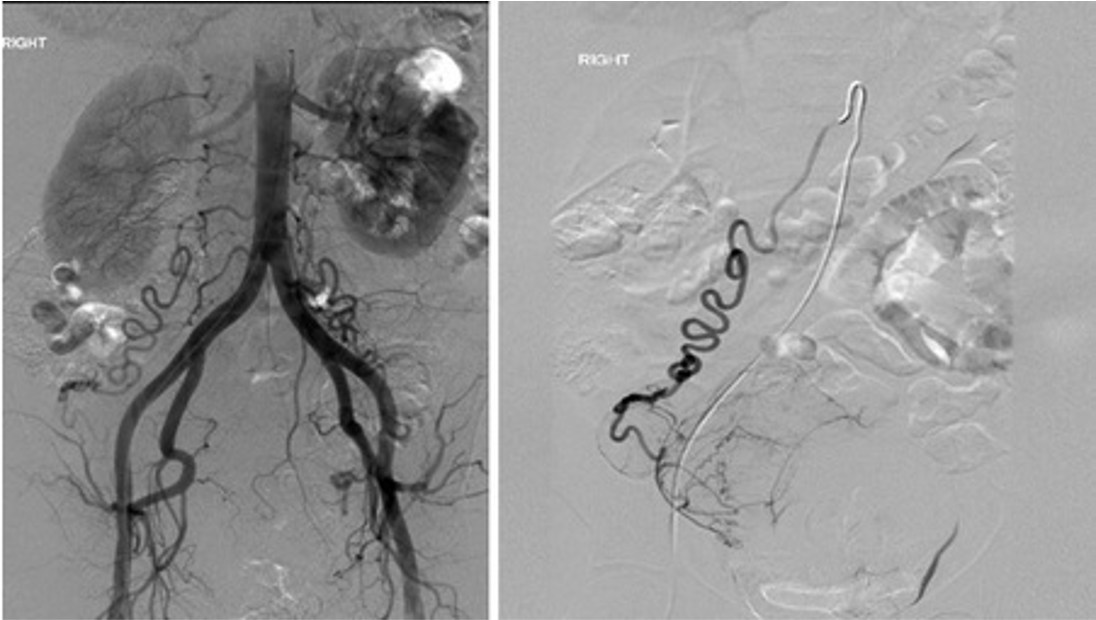

what is a potential complication of embolization of the selected vessel?

ovarian artery is selected in the right image.

Potential complication of ovarian failure

This is a pt with uterine fibroids with some blood supply coming from an enlarged ovarian artery

polyarteritis nodosa(PAN)

multiple small aneurysms in the right renal arterioles

this is an Aunt Minnie and diagnostic of PAN

associated with HBV and HCV